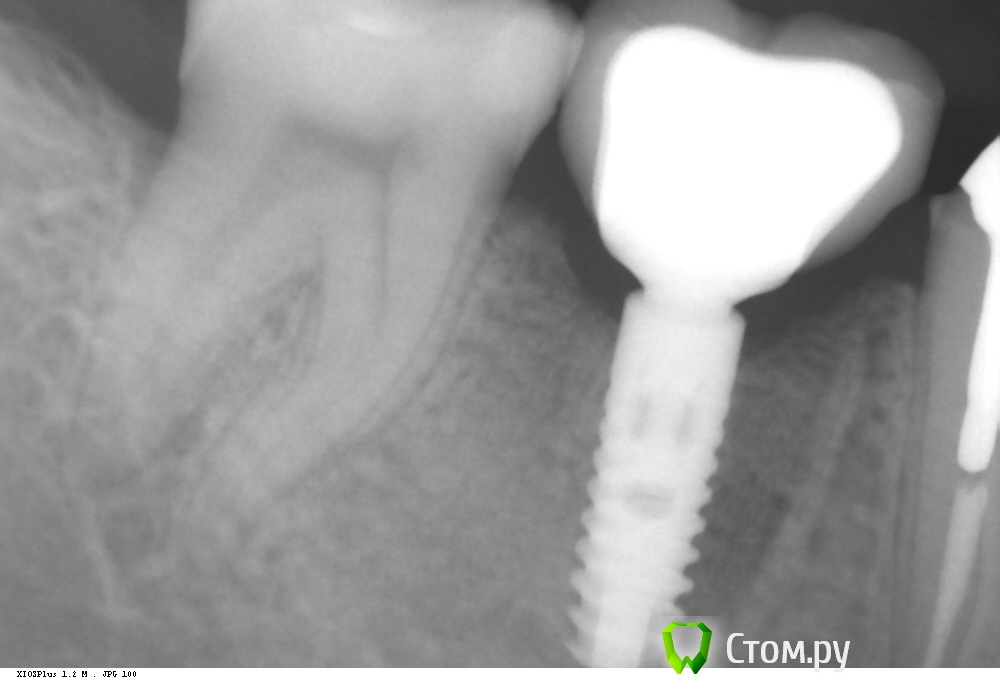

Dr.Sham Опубликовано 8 октября, 2014 Поделиться Опубликовано 8 октября, 2014 Удаление в другой клинике. КТ. Установка имплантата. кость была мягкая, но была со всех сторон по 2 мм минимум. Рентген оч жесткий. Через 2 месяца раскрытие имплантата, имплантат был окружен костью, как обычно, пришлось его раскапывать. ФДМ. Заживление без особенностей. Сегодня была фиксация коронки, сделал рентген для проверки фита. И...потерял дар речи. Десны маловато, но вокруг все кератинизировано. ФДМ узкий был. C чем может быть связана резорбция? Ссылка на комментарий

Dr.Sham Опубликовано 8 октября, 2014 Автор Поделиться Опубликовано 8 октября, 2014 IvanK, все стандартно было. не протоколировал.Я не буду ни с кем спорить, меня смущает именно кратер.А про заглубление, вот пример 2 года, полет нормальный. Ссылка на комментарий

Dr.Sham Опубликовано 8 октября, 2014 Автор Поделиться Опубликовано 8 октября, 2014 Полёт мог быть отличным, если бы мы видели кость на плечах имплантатов…Вы можете сильно обжечься при тонком биотипе, если не будете ставить глубже. Но это Ваше дело, учиться на чужих ошибках или на своих.Дмитрий, вы меня ине поняли. Я не спорю ни в коем случае про заглубление, что это нужно на анкилосе, я хотел показать как раз-таки то, что на последнем снимке тоже не заглубил, кость ушла, но кратера нет. Ссылка на комментарий